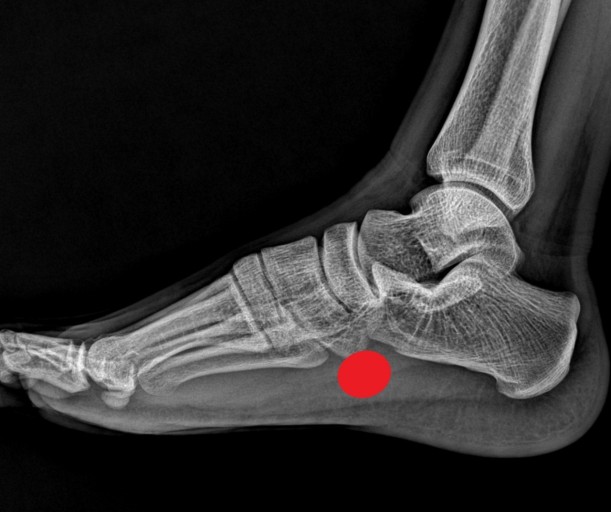

족저 근막염의 가장 흔한 증상은 발꿈치 통증입니다. 첫 걸음을 디딜 때 통증이 가장 심하며, 일상적인 활동 중에도 통증이 발생할 수 있습니다. 통증은 발꿈치 안쪽에서 느껴지는 경우가 많습니다.

족저 근막염 증상 5. 발바닥 아랫부분의 통증

발꿈치 외에도 발바닥 아랫부분에 통증이 발생할 수 있습니다. 통증은 주로 발꿈치에서부터 발바닥 중앙까지 느껴지며, 장시간 걷거나 서 있을 때 더욱 심해집니다.